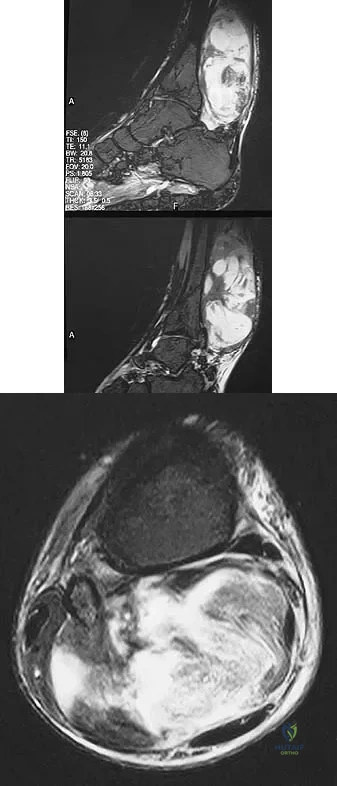

Figures 13a and 13b show the MRI scans of a 70-year-old patient who has a posterior calf mass. Examination reveals that the mass extends to the midcalf level. A biopsy specimen reveals a high-grade soft-tissue sarcoma. Metastatic work-up shows no lesions. Management should consist of

Explanation